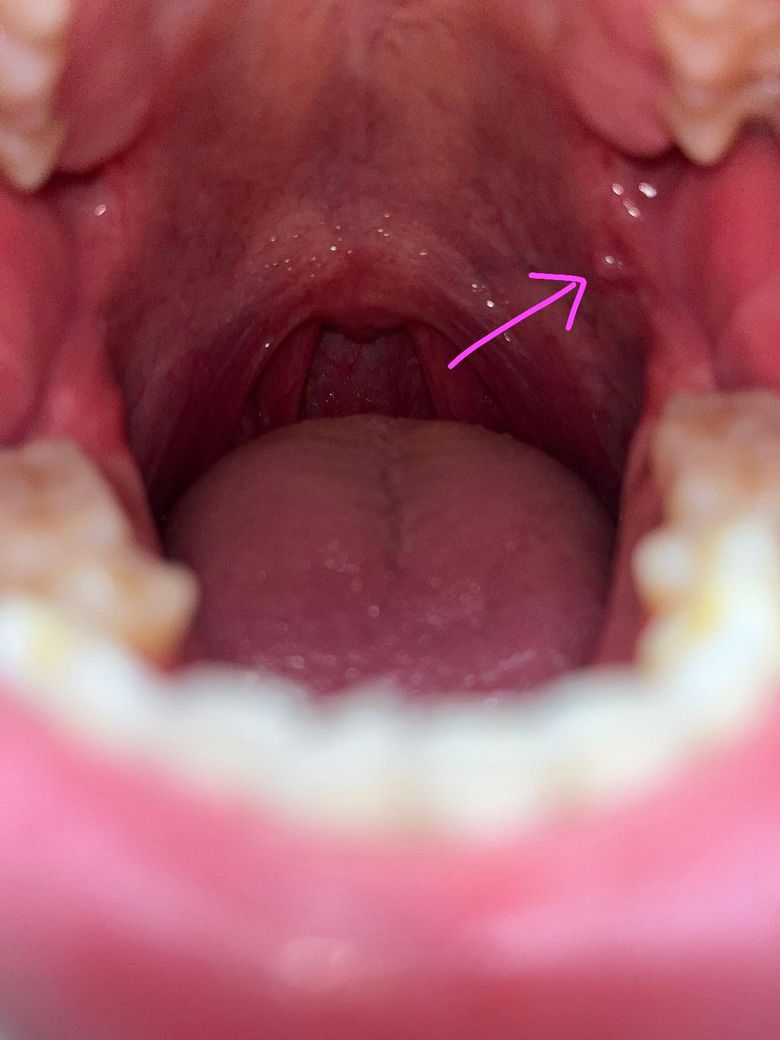

첨부된 사진으로는 우상단에 돌기가 생겼는데 아프진 않습니다.

누르면 통증은 살짝있고 조금 단단하네요

• 1번 째 사진